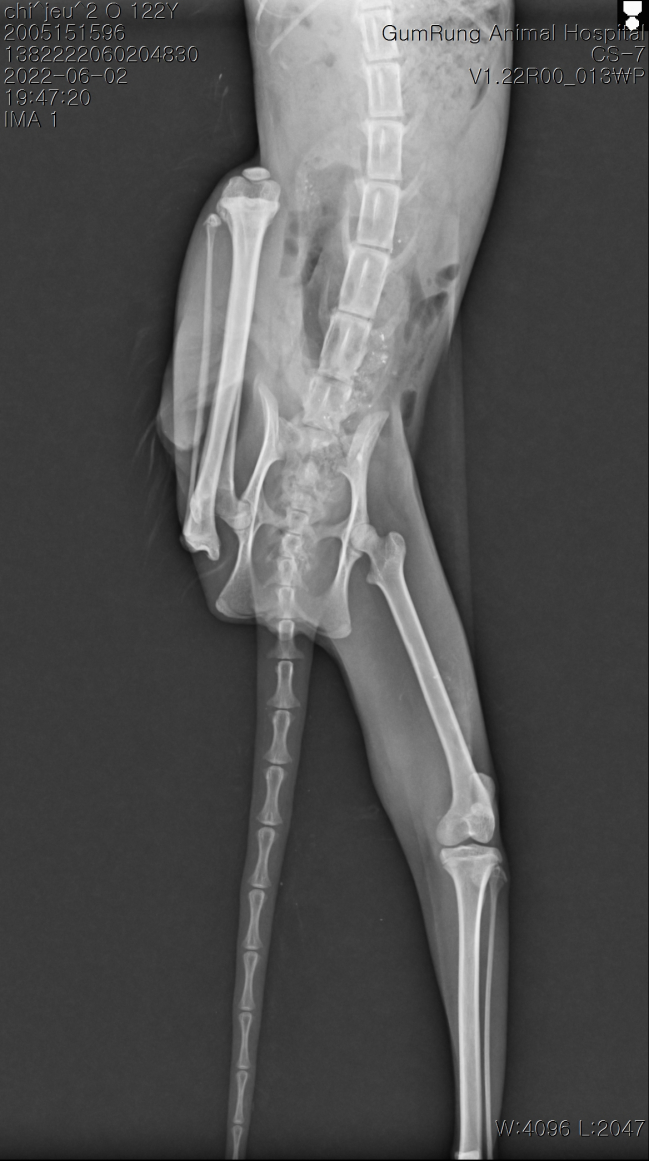

치아흡수성병변(구내염) 으로 인한 나비 구조 후 생활(나비)

요콩이 집에서 임시 보호하면서 잘 돌보고 있습니다.

하루하루 회복되는 모습이 짠하면 대견스럽네요.^^